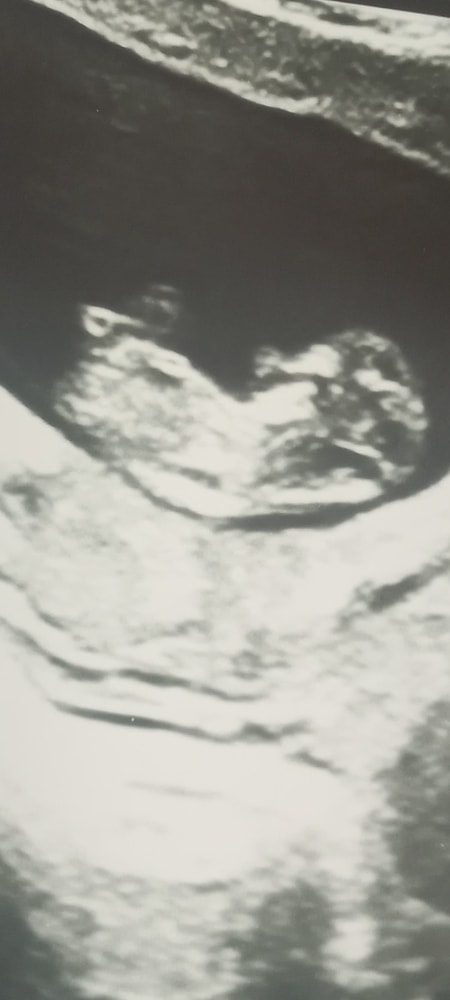

10+6 недель, фото узи

Наши будни, наши неделькиСдала сегодня кровь на нипт, выбрала стандарт. Уже только сдав кровь, мне намного спокойнее. Скрининг через неделю, ровно в 12 нед, поэтому результаты будут плюс минус. В 8.5 и 9.5 недель узи делали в стационаре, ни то что фото, даже экран не показали. И вот сегодня моё счастье показали на экране и дали фоточку. Там уже человек, машет руками и ногами, танцор😄

Ктр 38.6мм

Жм 4.9 мм

Чсс 169

По узи срок совпадает с акушерским))

Ноооо картина немного омрачена краевым предлежанием. Ещё рано ставить такой диагноз, матка ещё может подняться. Будем ждать хорошего исхода и беречь себя как зеницу)